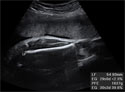

Ecografía Embarazo 4D - TERCER TRIMESTRE: Peso y tamaño del feto